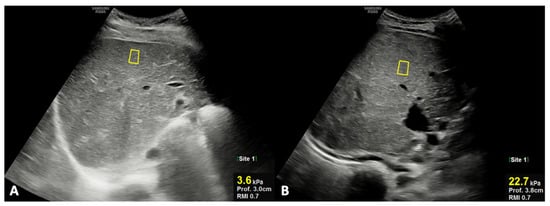

2.3. US and MR Imaging Acquisition and Processing

- Caruso, M.; Cuocolo, R.; Di Dato, F.; Mollica, C.; Vallone, G.; Romeo, V.; Petretta, M.; Liuzzi, R.; Mainenti, P.P.; Iorio, R.; et al. Ultrasound, shear-wave elastography, and magnetic resonance imaging in native liver survivor patients with biliary atresia after Kasai portoenterostomy: Correlation with medical outcome after treatment. Acta Radiol. 2020, 61, 1300–1308. [Google Scholar] [CrossRef]

- Caruso, M.; Di Dato, F.; Mollica, C.; Vallone, G.; Romeo, V.; Liuzzi, R.; Mainenti, P.P.; Petretta, M.; Iorio, R.; Brunetti, A.; et al. Imaging prediction with ultrasound and MRI of long-term medical outcome in native liver survivor patients with biliary atresia after kasai portoenterostomy: A pilot study. Abdom. Radiol. 2021, 46, 2595–2603. [Google Scholar] [CrossRef]

- Serai, S.D.; Trout, A.T.; Sirlin, C.B. Elastography to assess the stage of liver fibrosis in children: Concepts, opportunities, and challenges. Clin. Liver Dis. 2017, 9, 5–10. [Google Scholar] [CrossRef] [Green Version]

- Dillman, J.R.; Heider, A.; Bilhartz, J.L.; Smith, E.A.; Keshavarzi, N.; Rubin, J.M.; Lopez, M.J. Ultrasound shear wave speed measurements correlate with liver fibrosis in children. Pediatr. Radiol. 2015, 45, 1480–1488. [Google Scholar] [CrossRef]

| Liver stiffness (kPa) | 5.95 ± 1.28 | 10.47 ± 7.32 | 0.020 | |